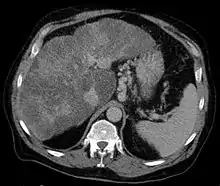

يتطلب تشخيص دوالي المعدة غالباً تنظيراً هضمياً علوياً. تشمل الأنواع الأخرى للتصوير المستخدمة لتشخيص دوالي المعدة التصوير المقطعي المحوسب (مع التباين)، الموجات فوق الصوتية عبر البطن مع دوبلر، تصوير الأوعية، تصوير الأوعية بالرنين المغناطيسي، و تصوير وريد الباب.[7]